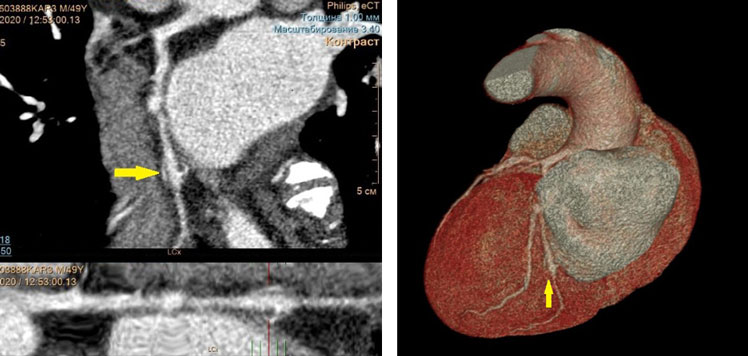

По данным КТ (Philips Ingenuity 128) на 2-е сутки госпитализации: умеренный кальциноз КА, индекс Агатстона 230; фузиформная аневризма в средней трети огибающей ветви левой КА 11×9,5 мм протяжённостью 16 мм с кальцинозом стенок и пристеночными концентрическими тромботическими массами, остаточный просвет 3,7 мм (рис. 1, 2); стеноз в проксимальной трети передней межжелудочковой ветви 50–55%, стеноз в проксимальной трети огибающей ветви левой КА 60–65%.

Рис. 1. Компьютерная томограмма, мультипланарная реконструкция. Фузиформная аневризма в средней трети огибающей ветви левой коронарной артерии с кальцинозом стенок и пристеночными концентрическими тромботическими массами (отмечена стрелкой)

Рис. 2. Компьютерная томограмма. Фузиформная аневризма в средней трети огибающей ветви левой коронарной артерии с кальцинозом стенок и пристеночными концентрическими тромботическими массами (отмечена стрелкой)

Вместе с тем, у данного пациента было обоснованным углублённое исследование коронарного русла с целью определения перспективности и необходимости планового чрескожного коронарного вмешательства. Проведённая с этой целью КТ выявила не только высокие степени стеноза в нескольких КА, но также и структурные изменения коронарного русла в виде аневризмы проксимального сегмента передней межжелудочковой ветви. Метод КТ позволил не только определить степень атеросклеротического поражения КА (индекс Агатстона) и их структурную патологию, но также и выявить наличие пристеночного тромбоза в полости аневризмы, что невозможно сделать по данным коронарной ангиографии.